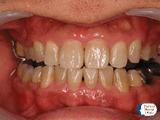

症例1

30代男性。口臭が極めてひどく、歯肉から出血、汚れや茶渋、歯石がたくさん付着していました。歯科衛生士による口腔ケア指導,超音波による歯石除去、クリーニングを数回にわたって徹底的に行ったところ,炎症を起こしてすぐ出血していた歯肉はピンク色に変わり、歯の表面もキレイでツルツルに、口臭もなくなりました。普段の口腔ケアも上手になり、現在も定期的にメンテナンスに通院されています。以前はよくカゼをひいていましたが今はほとんどなくなり健康になりました。口腔ケアの大切さがわかる症例です。

| 術前 | 術中 | 術後 |